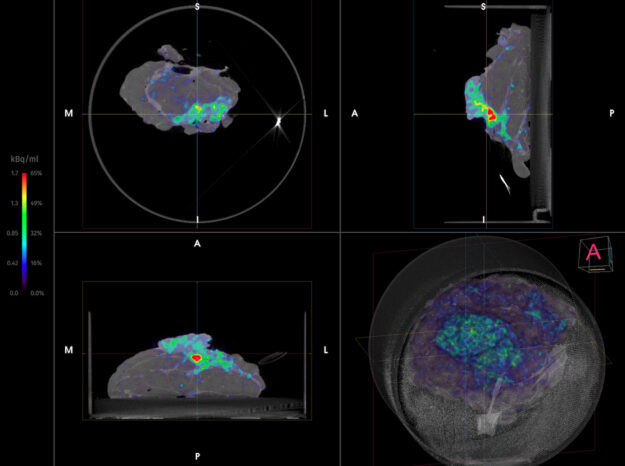

XEOS Aura 10 PET-CT | Potilastapaus 23: Okasolusyöpä retromolaarisessa trigonissa

Kliininen tutkimus | Kirurgia | Syöpätaudit | Potilastapaus Case 23: Squamous Cell carcinoma of the retromolar trigone (linkki englanninkieliseen artikkeliin tiivistelmän jälkeen) Tiivistelmä Hoidettaessa potilaan suun okasolusyöpää kirurgit pyrkivät saamaan marginaaliksi vähintään 5 mm. Monimutkaisen anatomian vuoksi voi olla vaikea olla varma, että kaikki resektiomarginaalit ovat vapaat, kun hoidetaan suun okasolusyöpää esimerkiksi retromolaarisella tai kitalaen…